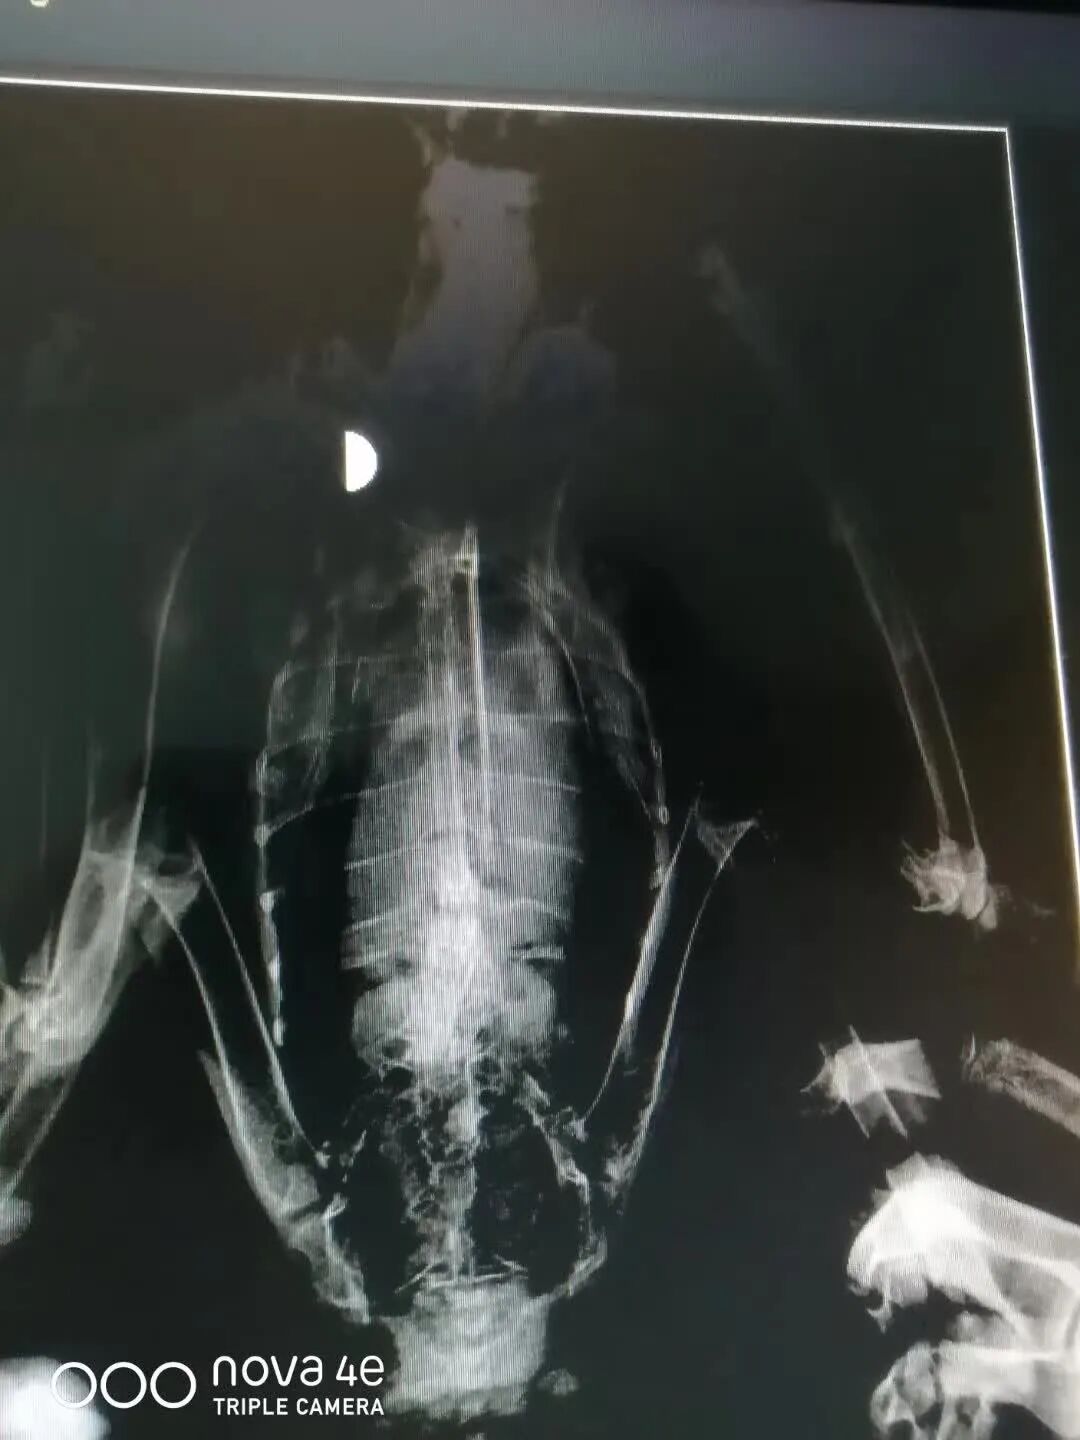

6月26日,双龙收到一只猎隼,由克尔伦苏木牧民交给林业公安局民警,后转交到救助站。经检查这只猎隼伤势特别严重,腰椎骨折,双腿没知觉,肛门附近很脏。

面对如此严重的伤势,双龙也束手无策,经过多方求救后,得到2种救治建议,第一安乐死,第二保守治疗。

被救助的猎隼伤势严重

双龙不忍心,选择了保守治疗,他希望发生奇迹,希望这只猎隼能够好起来!

虽然经过细心照顾和治疗,但这只猎隼最后还是没能好起来,令人遗憾。双龙最后的努力,也只能是让猎隼吃饱上路。

受伤猎隼骨折情况

救助受伤的野生动物,生死问题是双龙等一线护鸟人每天都面临的抉择。因为热爱动物而成为志愿者的他们,面对死亡需要更强大的内心,但他们一直在坚持。